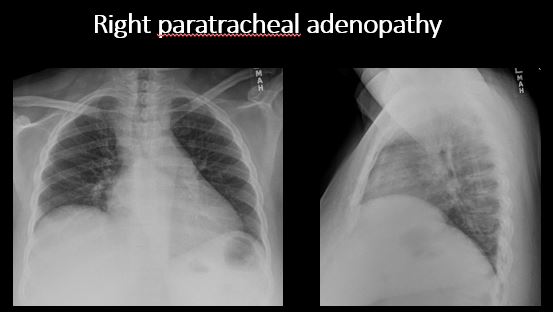

The right paratracheal stripe is thickened or enlarged. [Yes/No]